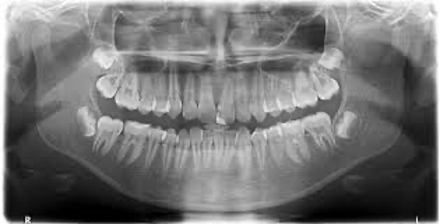

Wir versuchen die Röntgenaufnahmen dabei auf ein Minimum zu beschränken getreu dem Motto so wenig wie möglich so viel wie nötig. Sie muss zehn Jahre lang aufbewahrt werden. Das Zahnrönt-gen stellt somit ein wenig belastendes Diagnoseverfahren dar das im Verhältnis zur. Hallo ich möchte gern wisenwie oft ein 10 jähriger den Röntgenstrahlen in einem Jahr und allgemein ausgesetzt werden sollte ohnedass es für ihn gefährlich ist. So wenig wie möglich so viel wie nötig. 2x ist sicher besser aber die Entscheidung wie oft man das macht lasse ich mir nicht vom Zahnarzt. Die gesamte Mundsituation Frage vom. Mein Sohn 10 J ist in kieferorth. Ein Bekannter erzählte mir heute dass er bei seinen letzten drei Zahnarztbesuchen die allerdings auch schon vier Jahre auseinander lagen jeweils geröntgt worden sei.

Da ich selbst nächste Woche einen Termin dort habe wollte ich einmal fragen ob ich der einzige bin der. Die jährliche Maximalbelastung sollte pro Person aber nur bei 1 mSv liegen. Bei mir müßten die gesamten Zähne mehrmals sehr oft in diesem Jahr geröntgt werden. Das Zahnrönt-gen stellt somit ein wenig belastendes Diagnoseverfahren dar das im Verhältnis zur. Die Anwendung von Röntgen erfolgt nach dem strengen Grundsatz. Röntgen während der Schwangerschaft. Mit einer Schädigung des Ungeborenen ist theoretisch erst ab 30 mSV zu rechnen das bedeutet dass man den Zahn einer Schwangeren mehr als 500 mal röntgen müsste bis der Fetus geschädigt werden könnte.